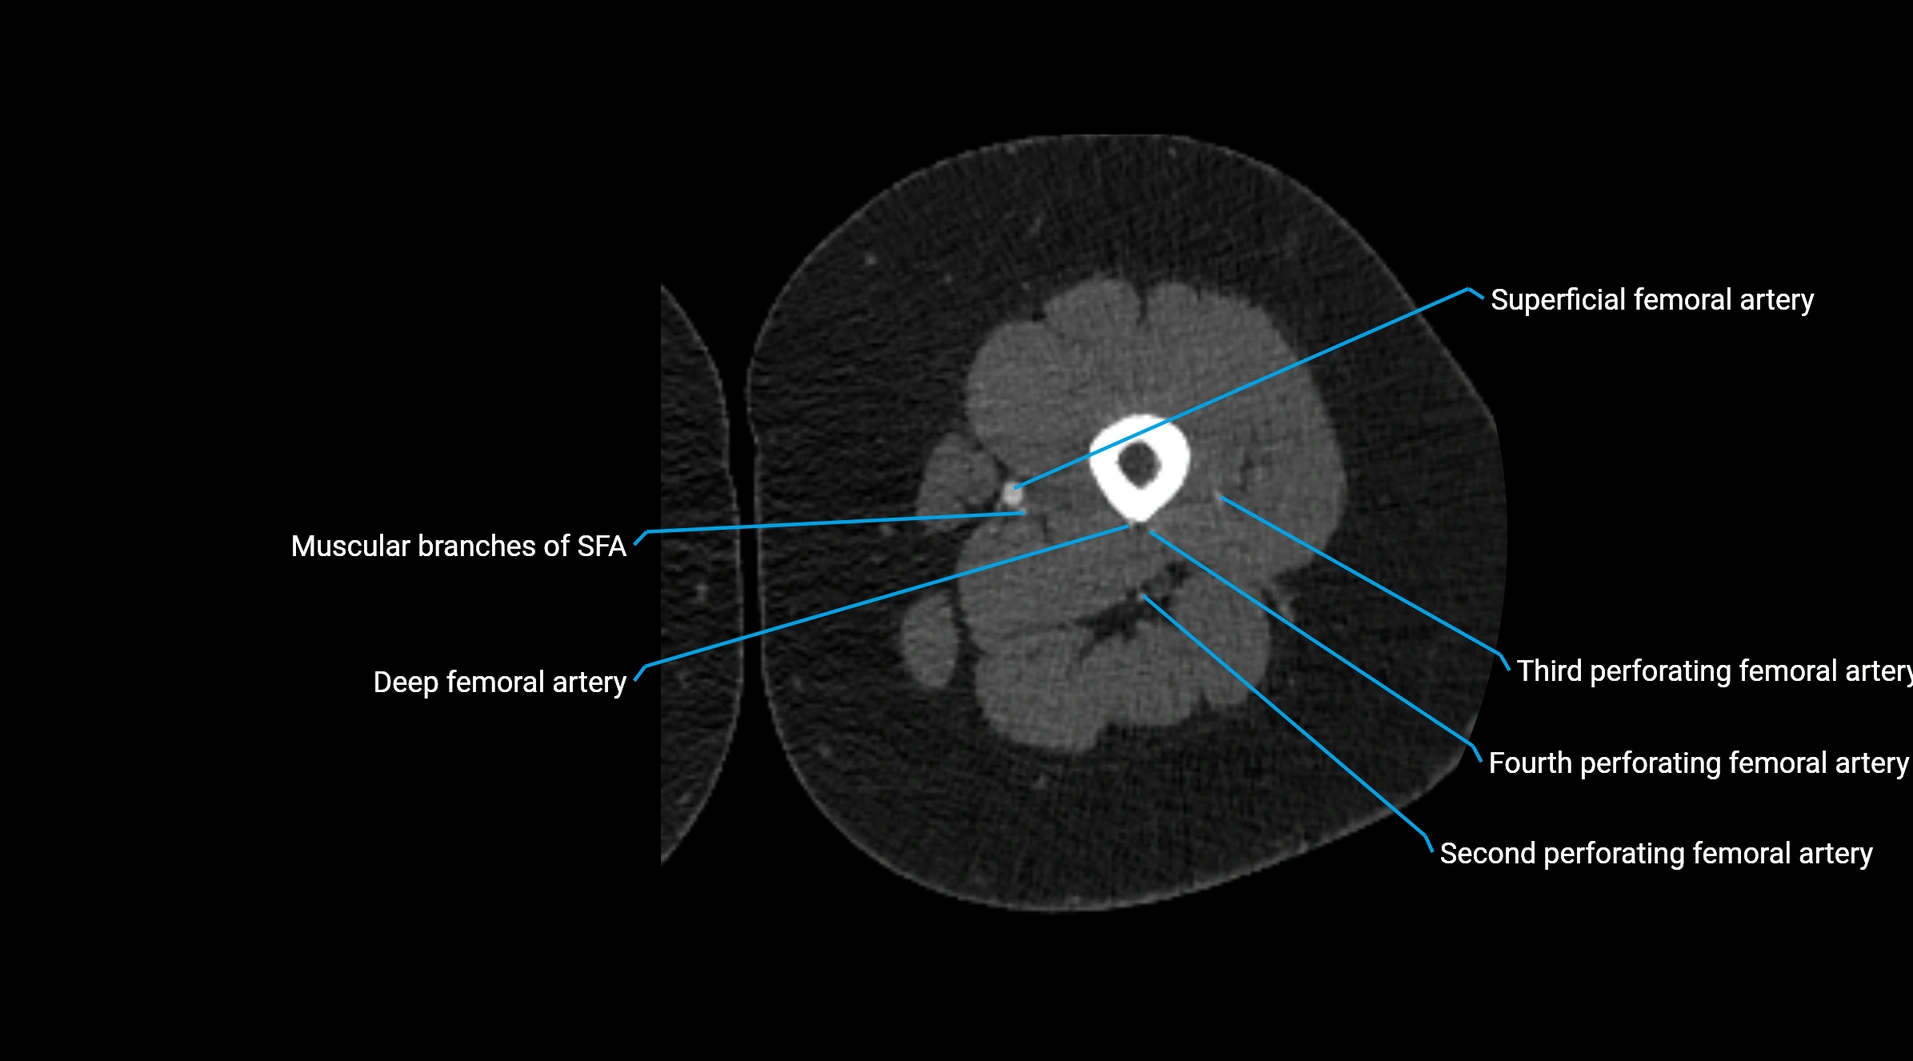

CT images

image